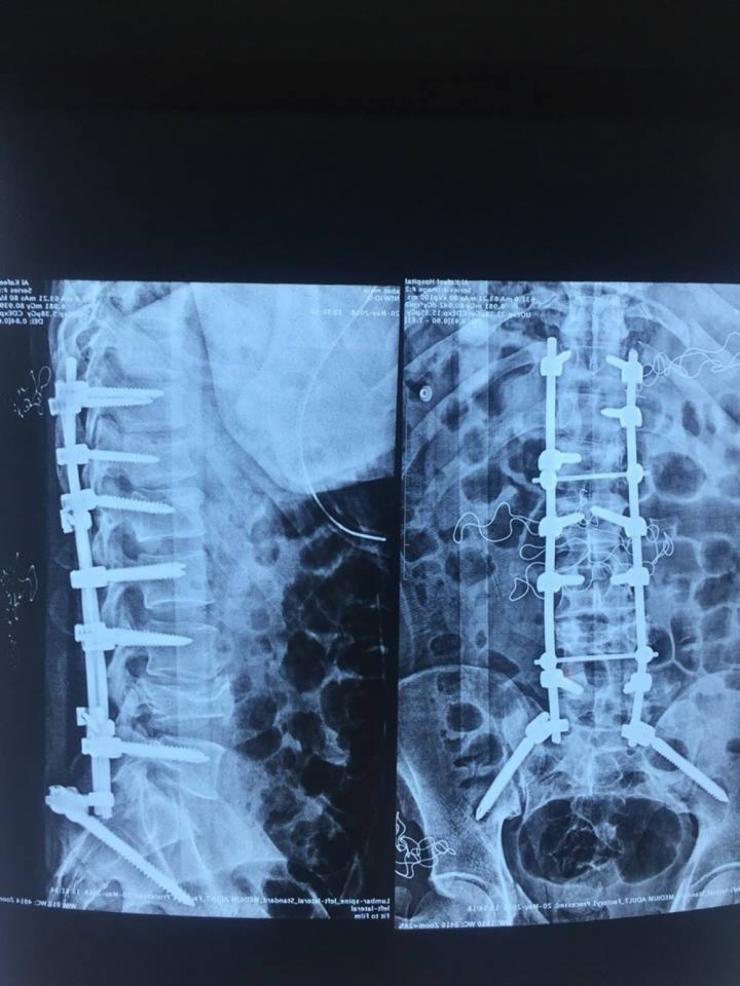

نتيجة تعرضه الى حادث سير.. انقاذ شاب عشريني من الشلل في مستشفى الكفيل الشاب العشريني تعرض الى حادث سير ادى الى كسر وتهشم اربعة من فقراته جعلته عاجز تماما عن الحركة ومهدد بالشلل. رئيس الفريق المعالج اختصاصي جراحة الجملة العصبية الدكتور خالد السراج، ان فريق طبي برئاستنا نجح بإجراء عملية لتثبيت كسر وتهشم اربعة فقرات وعظام الحوض لشاب من محافظة الديوانية بعمر 26 عاما. وبين السراج، ان الشاب كان قد تعرض لحادث سير ادى الى كسر الفقرة الصدرية الثانية عشر والقطنية الاولى والرابعة وعظام الحوض وتهشم احدى الفقرات العجزية، وكان بحالة حرجة جدا وقت وصوله للمستشفى ومعرض لقطع حبله الشوكي في حال تأخر اجراء العملية الجراحية له سريعا. وعد السراج، هذه العملية بانها نوعية في اختصاص جراحة الجملة العصبية نظرا لتعقد الاصابة وصعوبة اصلاح هذا النوع من الكسور والتهشم، مؤكدا على ان المصاب استعاد الحركة عقب العملية بوقت قياسي وتمكن من الوقوف والسير على قدميه. من جانبه ذكر الشاب العشريني، بعد تعرضي الى حادث السير اصبحت عاجز تاما عن الحركة وكنت قلق من اصابتي بالشلل وعند عرض حالتي على الطبيب في مستشفى الكفيل اخبرني بانه لابد من اجراء عملية جراحية مستعجلة. مبيناً، اجريت العملية الجراحية وتماثلت للشفاء خلال وقت قياسي والان انا اتمتع بصحة جيدة. يذكر أن واردات المستشفى تذهب بالكامل لتمويل خدماتها ورعاية المرضى الفقراء، إذ أن ارتفاع أسعار العمليات هو بسبب ارتفاع سعر الأجهزة المتطورة والتي تضاهي ما موجود عالمياً وهي تتطلب ادامة مستمرة، وهذا يحتاج مبالغ كبيرة. كما أن جميع العمليات التي تجرى في المستشفى يقوم بها أطباء متميزون ومختصون إزاء نسبة معينة من المبلغ الذي يدفعه المريض، وهم من العراقيين والمغتربين والاجانب من ذوي الخبرة والنجاحات العالمية. أما الجزء الثاني من مبلغ العملية الذي يدفعه المريض، فيذهب لتغطية رواتب العاملين والاطباء المقيمين والممرضين، وتغطية مصاريف المستشفى من الكهرباء والماء وخدمة المعامل الخدمية التابعة للمستشفى، وخدمات الجباية الحكومية، إضافة إلى تمويل تذاكر وتأشيرات واقامة وحماية الاطباء الاجانب المستقدمين من الخارج. وما يتبقى من حصة المستشفى يغطي مشروع (اطباء بلا اجور)، الذي يهدف لمساعدة المرضى الفقراء والحشد ومن كل الفصائل، ومشروع (التخفيض) الذي يتكفل إجراء العمليات لفقراء المرضى بشكل مجاني أو بتخفيض الكلفة لنصفها او ثلثها. رشا/الخالدي